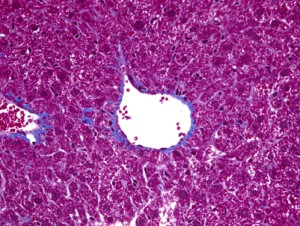

Masson-Trichrome染色による線維化の検出(肝臓)

BNCTはホウ素をがん細胞に取り込ませ中性子を照射することで核反応を起こし、発生した2つの重粒子でがん細胞を破壊する放射線治療の一種です。生物学的手法によるBNCTの治療成績向上について検討を行っています。細胞実験及び動物実験にて腫瘍に対する殺傷能力・腫瘍縮小効果を検証し、さらに正常組織への影響についても研究を行います。(玉利勇樹)